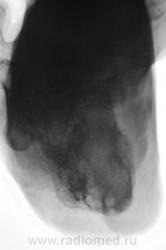

остиомиелита не видно а вот шпора знатная..

остеомиелит пяточной кости.

Валентин Львович, так всё-таки расценили как остеомиелит?.. Не увидел периостальной реакции, смазанности/лизиса (участков) кости, а вижу уплотнение мягких тканей (качество снимка, не отёк)...

Остеомиелит. Есть краевая деструкция бугра, чередование пороза/склероза.

Лечат от остеомиелита, но безуспешно. По всей видимости, пациент поедет в областную.

Валентин Львович, будьте любезны, опишите местный статус, насколько давно возникла клиническая картина. По снимкам - согласна с Сан Санычем: скорее - ткань, чем +ткань, т.е. есть ли изъязвления, открытая раневая поверхность. Поясняю6 такая картина м.б. не только при гнойно-воспалительных процессах, но и при опухолях кожи (например - плоскоклеточный рак, меланома). Длительно существующие воспалительные процессы нередко сочетаются (или осложняются) с опухолью, по-видимому происходит постепенная метаплазия.

Да, имеется изъязвленная поверхность, из которой выделяется не приглядного вида содержимое, весьма дурно пахнущее, процесс существует около 1,5 лет. Наши хирурги лечат или не лечат - не знаю, сейчас, данный пациент лечится амбулаторно, ранее, около месяца находился в хирургическом отделении.